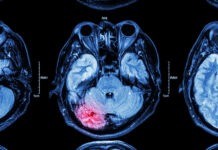

Щороку жертвами інсульту стають понад 100 тисяч українців, третина з яких – молодше 65 років. В Україні, у порівнянні з країнами Європи, не лише...